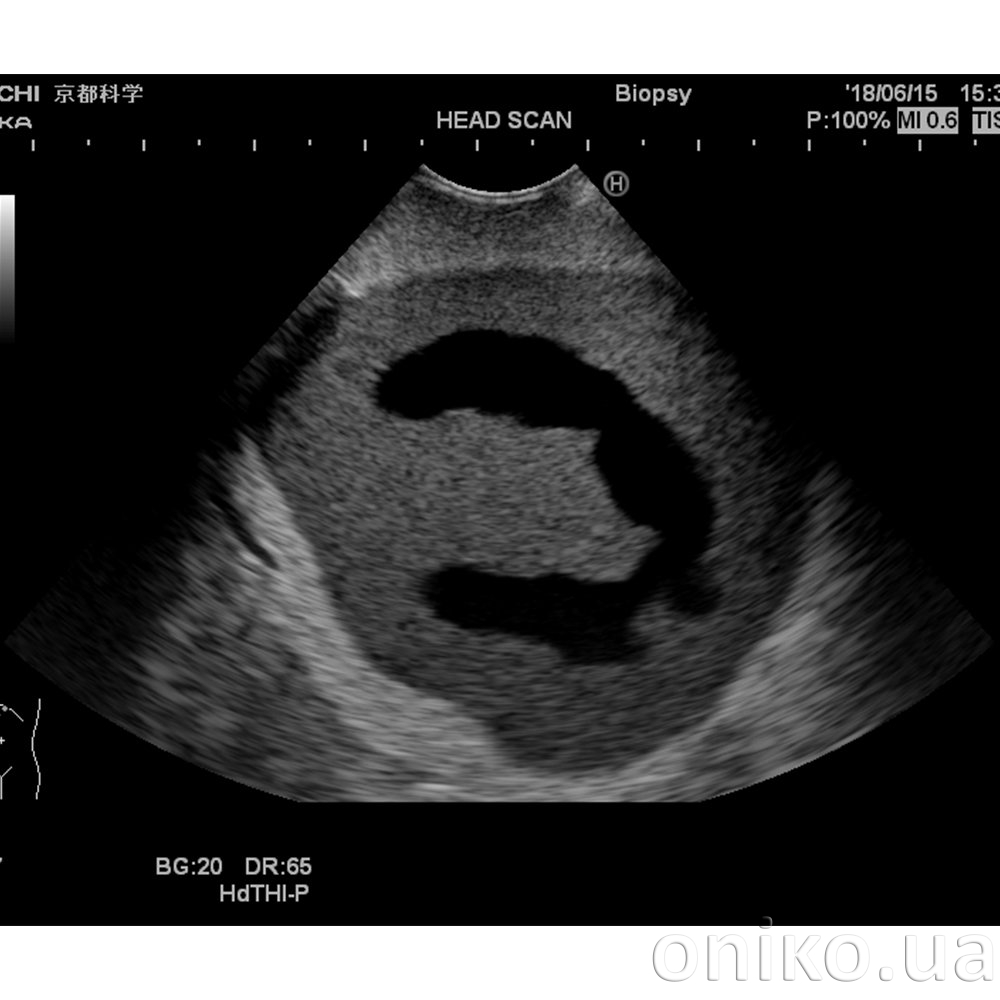

Ultrazvukový Fantom hlavy novorozence (typ-patologie)

První ultrazvukový Fantom hlavy novorozence s hydrocefalem na světě

Tento Fantom hlavy je navržen tak, aby vykazoval abnormální anatomii, jako je hydrocefalus; tvar lebky se změnil v důsledku intrakraniálního tlaku.

- Hypertrofovaná laterální komora